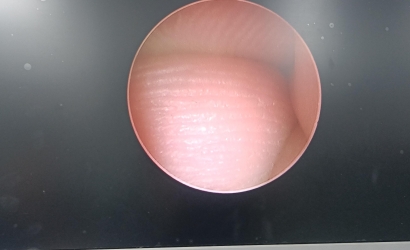

• 宮腔鏡常見故障及排查方法及YOUSHI宮腔一體鏡Y2052的維修案例

宮腔鏡常見故障及排查方法及YOUSHI宮腔一體鏡Y2052的維修案例